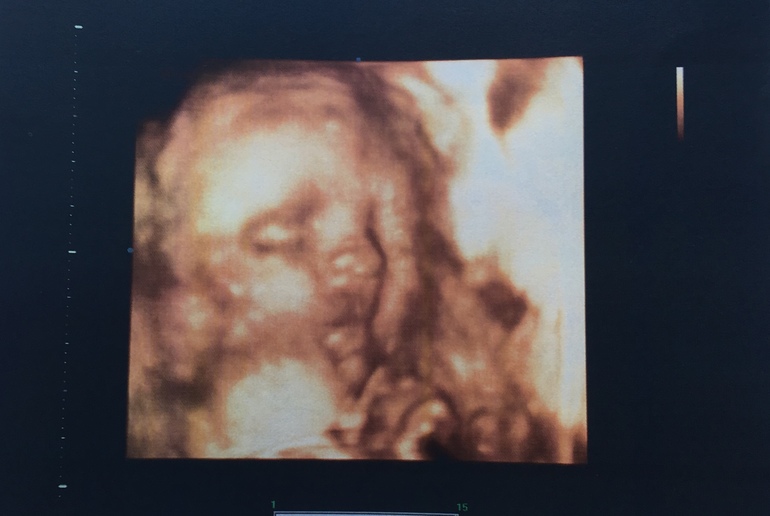

3Д УЗИ в 25+5 😍

Нам 25+5 и мы прошли очередное УЗИ. Папа первый раз ходил смотреть пупсика и умилялся. Ещё бы. Щекастая и губастая в него 😍3Д на память - рекомендую, я сначала сомневалась делать или нет.

Дада, девочку подтвердили!

Мы миниатюрные, но милыыыыыые. Целых 790гр, 32см. И вот такие пупсики ☺️